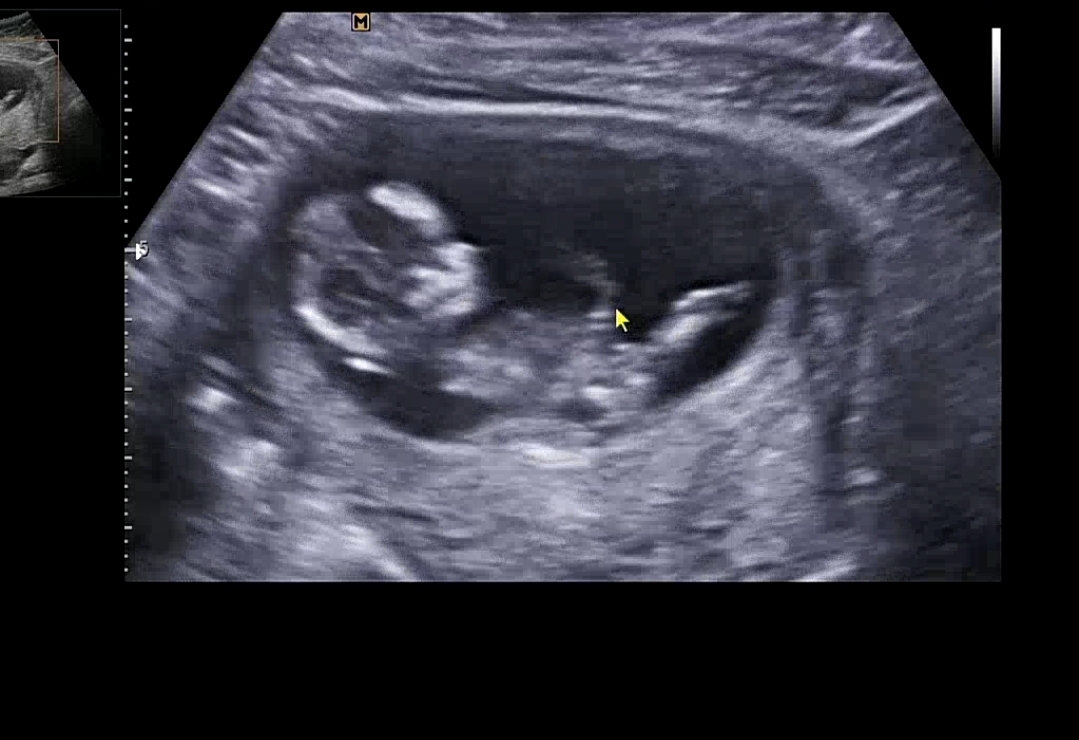

12주3일차 딸일까용?

다리사이에 뭐가 없어보이긴하는데 아직 잘 모르려나용? ㅎㅎ

제 눈에는 딸 처럼 보여요 ㅎㅎ